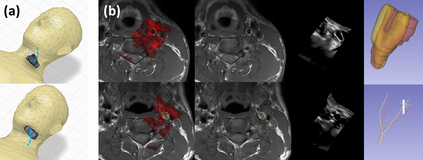

Purpose: Trans-oral robotic surgery (TORS) using the da Vinci surgical robot is a new minimally-invasive surgery method to treat oropharyngeal tumors, but it is a challenging operation. Augmented reality (AR) based on intra-operative ultrasound (US) has the potential to enhance the visualization of the anatomy and cancerous tumors to provide additional tools for decision-making in surgery. Methods: We propose and carry out preliminary evaluations of a US-guided AR system for TORS, with the transducer placed on the neck for a transcervical view. Firstly, we perform a novel MRI-transcervical 3D US registration study. Secondly, we develop a US-robot calibration method with an optical tracker and an AR system to display the anatomy mesh model in the real-time endoscope images inside the surgeon console. Results: Our AR system reaches a mean projection error of 26.81 and 27.85 pixels for the projection from the US to stereo cameras in a water bath experiment. The average target registration error for MRI to 3D US is 8.90 mm for the 3D US transducer and 5.85 mm for freehand 3D US, and the average distance between the vessel centerlines is 2.32 mm. Conclusion: We demonstrate the first proof-of-concept transcervical US-guided AR system for TORS and the feasibility of trans-cervical 3D US-MRI registration. Our results show that trans-cervical 3D US is a promising technique for TORS image guidance.